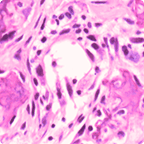

Abnormal mitosis

Perineural tumor invasion